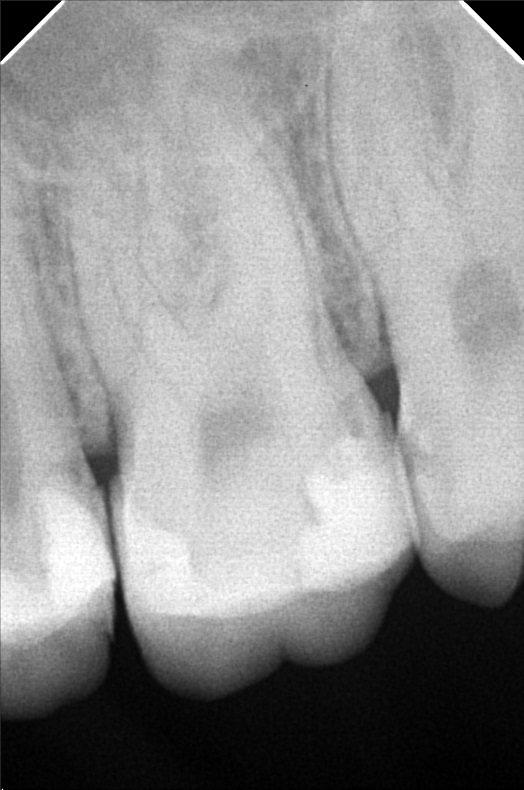

Edit Record Check our patient data records. Add patient information Patient Info Profile picture Last Name First Name Middle Name Birthdate Age Street Barangay City Country Zip Code Contact number Email Procedure 10/13/21- 26 LC with MTA MOD 23 Lingual Distal 11/24/21 - 25/27 LC# 27 #15 IRM -/Xray 03/16/22- zircinia prep on 15/16 shade: a3 body, cervical b3 digital impression done temporary crown done LC mesial 15, distal 14 xray on 24 3/25/22- installation 15, 16 zirconia opening of canal 24 TF with EUgenol 03/30/22 Lingual 18/ Buccal 19 Formocresol Incision and drainage Laser rx: co amoxiclav 625 mg/ mefenamic 500 mg 04/29/22- lingual 16.5mm buccal 19mm 05/04/22- obturation/ LC 8/12/22 - tooth prep #24 8/18/22- Cementation zirconia crown #24 8/26/22 - xray, intraoral radiograph 05/12/23- OP(L) 05/19/23- Xray/ Ozone/Resto - #21(mesial & lingual) 09/10/24 OP w/ air polisher 07/19/25 op with air polisher + fluoride 03/18/26 OP 04/08/26 #48 - Occ mesial MTA Fiber Biomimetic File delprado26.jpg File 2 delprado23-24-25.jpg File 3 6afb059c-2de8-4dc8-ac4d-ae6435b6dabc.jpeg File 4 katherine_del_prado.jpg File 5 katherine_del_prado_02.jpg File 6 katherine_del_prado_03.jpg File 7 File 8 File 9 File 10 File 11 File 12 File 13 File 14 File 15 File 16 File 17 File 18 File 19 File 20 Retain Record Retain Record Yes No Save Your Changes